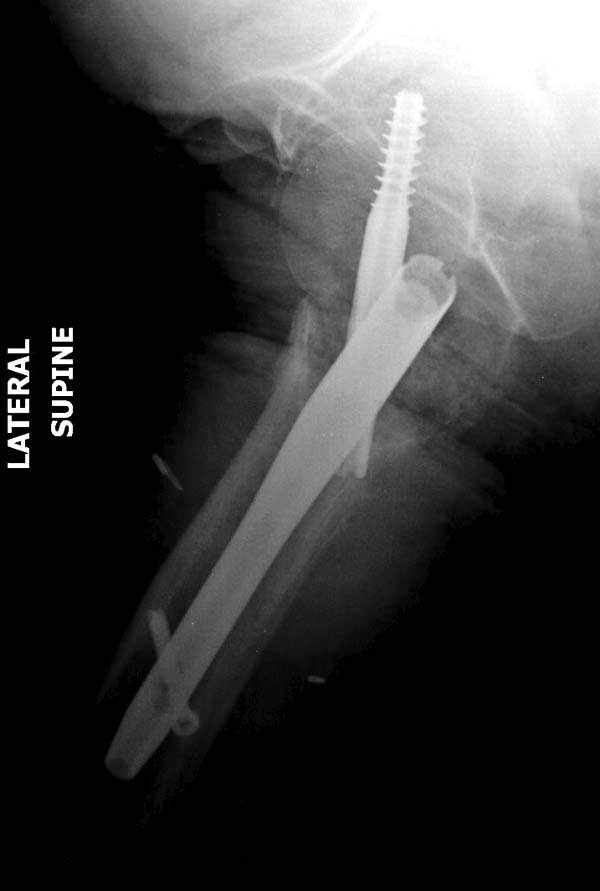

В зависимости от дистанции линии перелома и латерального кортекса надо использовать разной длины barrel, т.е. конец баррели не должен доходить до пределов перелома. Здесь конец длинного ствола упирается в медиальный фрагмент, что мешает созданию компрессии, а более короткий barrel создал бы запас для компрессии. В боковой пластине вместо 4х можно было ограничится двумя шурупами, потому что головка шурупа в 4.5 мм выдерживает давление до 350 кг.

Вторая операция- это фаза сохранения головки бедра. Желательно приложить все усилия и сохранить головку, но, как видно, “фиаско” продолжается. Здесь вместо нейтрализации сил между медиальной и латеральными сторонами была попытка удержать варус. Варус не удержать ни деротационными шурупами о котором говорили и не костными стружками вбитые в шейку, потому что вся нагрузка упирается в головку.